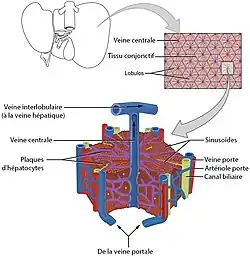

|

| Foie humain, vue supérieure |

|

| Foie humain, vue inférieure |

Le foie est constitué de cellules hépatiques (hépatocytes) organisées en travées autour des sinusoïdes (capillaires hautement perméables où le sang circule). L'unité fonctionnelle du foie est le lobule hépatique. Ses échanges avec le reste du corps se font pour la plupart à travers sa double irrigation sanguine (veine porte et artère hépatique propre), qui se termine par une multitude de capillaires jusqu'à l'intérieur du foie. On peut rajouter que plusieurs shunts se font entre le système porte et la veine sus-hépatique.

Les cellules hépatiques sont groupées à l'intérieur du foie en formations spéciales, les lobules hépatiques. Les lobules hépatiques sont donc des groupements de cellules hépatiques, de forme polyédrique, dont l'agencement est déterminé par la disposition des vaisseaux et des voies biliaires intrahépatiques. Les lobules hépatiques sont séparés les uns des autres par des travées de tissu conjonctif, auxquelles on donne le nom d'espace-porte ou espace de Kiernan, où cheminent des vaisseaux et des canaux biliaires intrahépatiques.